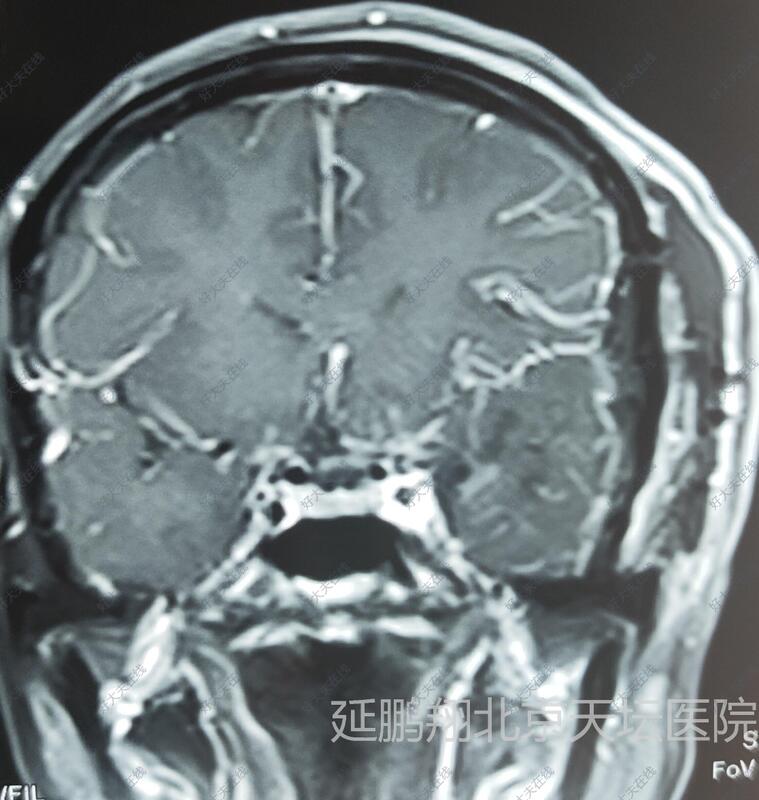

- 治疗后6天

术后病人恢复顺利,睡眠,进食,精神状态,行走均正常。常规复查核磁,显示肿瘤消失。